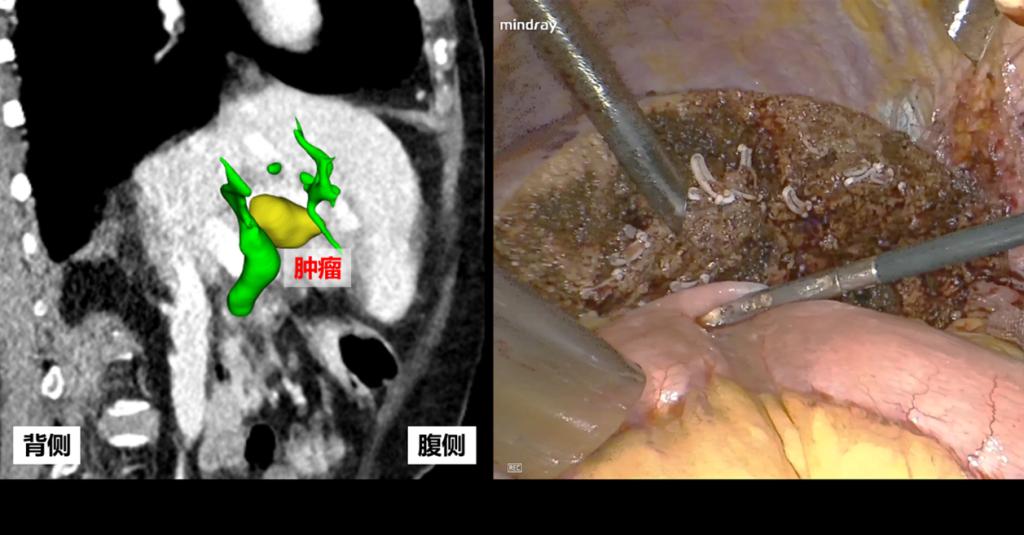

为了进一步寻找治疗机会,赵奶奶和家人慕名来到西安交通大学第二附属医院。肝胆胰与肝移植团队的接诊医师曲凯副主任医师仔细查看了赵奶奶的检查资料,发现赵奶奶仍然存在手术机会。不仅如此,凭借娴熟的腹腔镜手术技术,肝胆胰与肝移植团队还准备为赵奶奶实施腹腔镜下肝门部胆管癌根治术。

腹腔镜下实施肝门部胆管癌切除对于外科医生有着较高的要求,需要对肝门部解剖、切肝技巧以及胆肠吻合技术具有相当丰富的经验。考虑到患者年纪较大,基础疾病多,术前还邀请了肝病科、肿瘤科、影像科、麻醉科进行多学科会诊,为实施手术做好充分准备。

在刘昌主任医师精心指导下,曲凯副主任医师带领团队与麻醉团队、手术护理团队通力合作,顺利完成联合左半肝切除的腹腔镜肝门部胆管癌根治术。术中多次送检胆管切缘,直至手术切缘完全阴性,实现肿瘤R0切除。